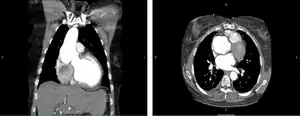

Before the operation, preparations include transthoracic echocardiography and measurements of the ascending aorta and the pulmonary valve.[10] Under general anaesthesia, the chest is cut open in the midline.[5] The heart and aorta are exposed before the heart is temporarily stopped and its function taken over cardiopulmonary bypass.[5] Subsequent steps include removing the diseased aortic valve and mobilizing the coronary arteries, followed by harvesting and preparing the person's own healthy pulmonary valve, before implanting it within the left ventricular outflow tract, the exit of the left side of the heart (where the aorta begins).[2][10] Then the coronary artery is reimplanted, before the pulmonary homograft is implanted in the right ventricular outflow tract, the exit of the heart's right side (where the pulmonary artery begins).[2][10] The pulmonary autograft is joined with the ascending aorta.[2][10]

After the operation, good blood pressure control prevents early dilatation of the new aortic root and allows the pulmonary autograft, now in the aortic position, to settle in its new environment.[10] Aftercare includes regular echocardiography and lifelong endocarditis prophylaxis.[2]